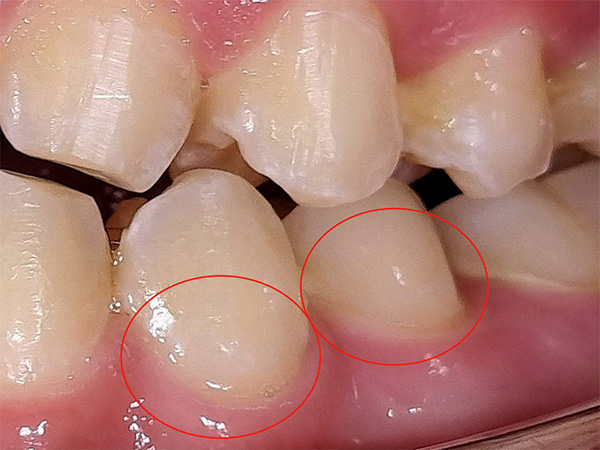

歯の白濁(ホワイトスポット)をICON治療で改善した症例

患者様は、歯の表面に見られる白い濁り(ホワイトスポット)を気にされ来院されました。

診査の結果、左下4・5の歯頚部付近にホワイトスポットが認められました。

ホワイトスポットは、エナメル質の脱灰などにより歯の内部構造が変化し、光の反射の違いによって白く見える状態です。

ICON(アイコン)治療を行いました。

ICONは、歯を削らずに専用の樹脂を浸透させることで、ホワイトスポットを目立ちにくくする治療法です。

歯質の侵襲を抑えながら、審美性の改善を図ることができます。

処置後は、白濁が目立ちにくくなり、周囲の歯となじんだ自然な見た目へ改善されました。